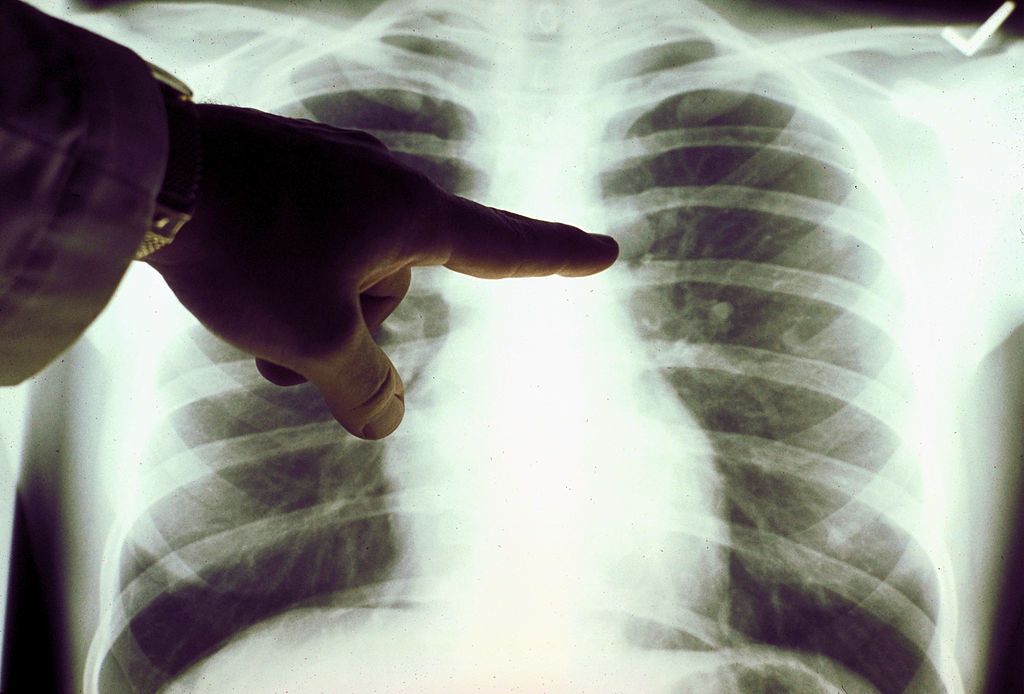

كشفت مجموعة من الصور للأشعة المقطعية والأشعة السينية للرئتين الخاصة ببعض المصابين بوباء “كورونا“، العديد من التشوهات التي يسببها الفيروس في الرئة، وهي شبيهة إلى درجة كبيرة لتلك التشوهات التي أحدثها فيروس “السارس”، وتلك الناجمة عن فيروسات متلازمة الشرق الأوسط التنفسية MERS. وأظهرت الصور وجود بقع في الرئتين، وهي التي قد تمكّن الخبراء من تشخيص أسرع وتساعدهم على منع العدوى أيضاً.

وكشف التصوير المقطعي لامرأة تبلغ من العمر 54 عاماً، بقعاً بيضاء في رئتيها، وقد أطلق العلماء عليها اسم “العتامة”. كذلك، أبرزت الصور المقطعية التي أجريت على صدر مريض صيني يبلغ من العمر 44 عاماً، وكان يعمل في سوق ووهان للمأكولات البحرية، وجود بقع في رئتيه. وكان الرجل نفسه قد احتجز في المستشفى بعد إصابته بحمى شديدة وسعال لمدّة أسبوعين تقريباً في ديسمبر/كانون الأول الماضي، وجرى تشخيص إصابته بالالتهاب الرئوي الحاد ومتلازمة الضائقة التنفسية الحادة، وتوفي بعد ذلك بأسبوع.

وفي مقاطعة سيتشوان في الصين، جرى تشخيص امراة تبلغ من العمر 45 عاماً بعد عودتها من اليابان، حيث تبين أنها أصيب بالحمى والسعال وآلام في الصدر، وكشفت الأشعة وجود بقع بيضاء واسعة النطاق في الرئة.

ولفتت دراسة حديثة أنّ “الأشعة المقطعية للصدر كانت أفضل من الاختبارات المعملية فى تشخيص كورونا بمرحلة مبكرة”. ومع هذا، فقد أكد الباحثون أن “الأشعة المقطعية يجب أن تكون طريقة الفحص الأولية للاشتباه فى كورونا”.